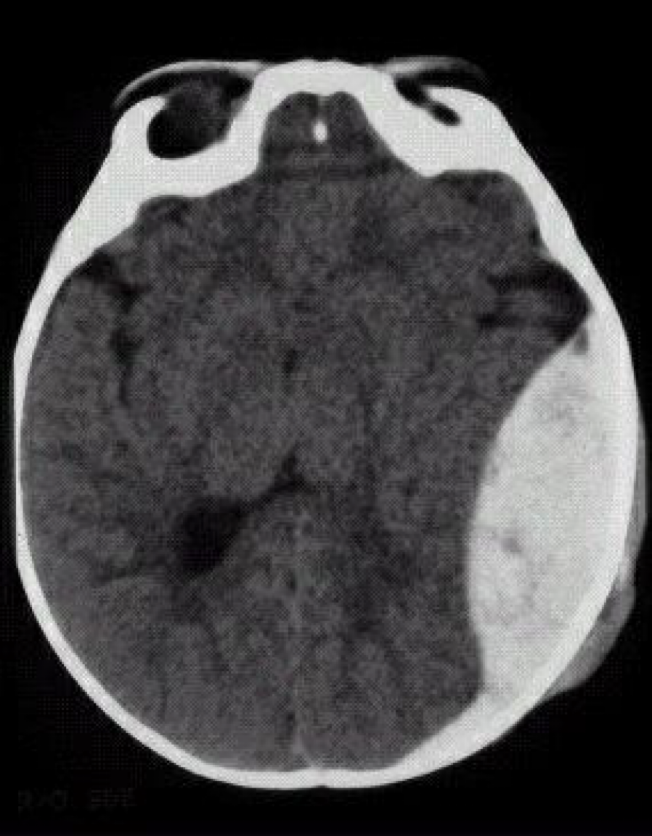

Subdural bleeding

(between the brain and dura mater)

acute, subacute, chronic

Variable latency of the development after head trauma: from hours to months.

Venous origin („bridging veins”, on the superior brain surface).

Skull fracture is not necessary.

Symptoms: less rapid, sometimes insidous growth.

non specific (headache, hemiparesis, dementia, seisures)

Diagnostics: CT.

Treatment: surgical removal.